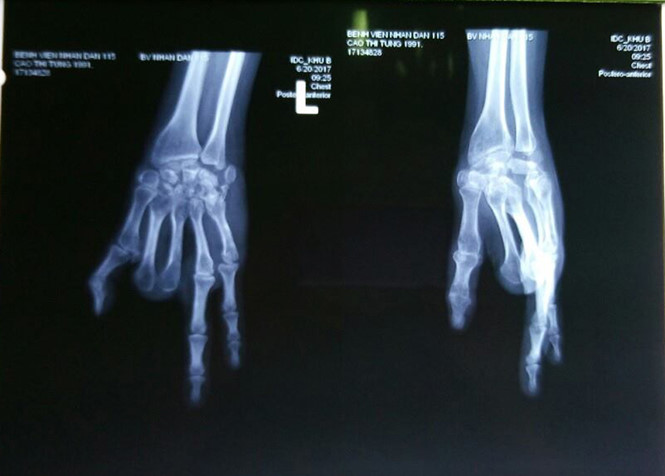

Phim chụp X-quang bàn tay của bệnh nhân bị cụt mất 2 ngón

Bệnh nhân là chị C.T.T (26 tuổi), cách đây 7 năm bị tai nạn lao động khi làm thêm ở xưởng nhựa khiến bàn tay bên trái bị dập nát, đứt lìa. Khi đó, các bác sĩ đã phẫu thuật ghép nối giữ lại được 3 ngón tay cho bệnh nhân. Tuy nhiên, do tổn thương quá nặng nên các ngón tay không còn chức năng vận động, cầm nắm.

“Bệnh nhân đã đến bệnh viện gặp bác sĩ khám và mong muốn được chuyển hai ngón chân lên bàn tay để bàn tay đủ 5 ngón và phục hồi vận động các ngón còn lại. Bàn tay cô gái đã mất hết chức năng, hệ thống gân duỗi và gân gập, thần kinh đã hỏng nên các ngón cứng, liệt không cử động bình thường được”, bác sĩ Viễn cho biết.